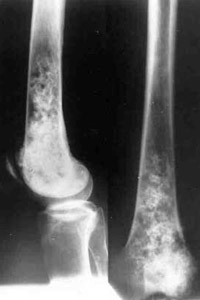

Tumour lower/third of right hip.

Removal of tumour with replacement of defect by means of Ilisarov's apparatus.

Closing of knee-joint.

Results of treatment.